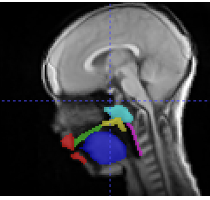

This study compared four multi-atlas segmentation methods for dynamic speech MRI and found that Corrective Learning achieved the best performance for segmenting the tongue, velum, and adenoid. Its accuracy improved as more temporal frames were used, supporting its potential to replace manual segmentation in small, specialized pediatric datasets.

Multi-Atlas-Based Segmentation of Pediatric Vocal Tract Anatomy in Dynamic MRI

H. Kang et al.

Journal of Speech, Language, and Hearing Research (2026)